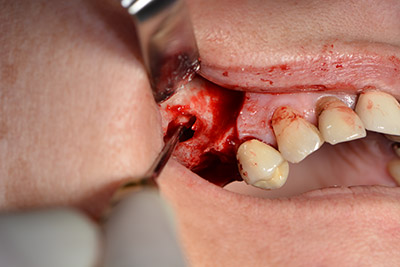

Surgical procedure for implantation

pilot drilling

Image 9: Overview and setting for pilot drilling.

The classic incision (crestal, buccal relief) and the preparation of the mucoperiosteal flap enabled a good overview.

Sky implants (bredent) were used this case. The surgical protocol of these, specify pilot drilling at about 1200 rpm (Fig. 9).

The following holes were drilled at a reduced speed of 300 rpm. The Implantmed demonstrated its true capability at this stage. The surgical protocol can be preset – the various positions can be selected simply by pressing the “P” position of the foot control (Fig. 10 to 11).